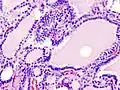

Hyperthyroidism is one of the most common endocrine conditions affecting older domesticated housecats. In the United States, up to 10% of cats over ten years old have hyperthyroidism.[63] The disease has become significantly more common since the first reports of feline hyperthyroidism in the 1970s. The most common cause of hyperthyroidism in cats is the presence of benign tumors called adenomas. 98% of cases are caused by the presence of an adenoma,[64] but the reason these cats develop such tumors continues to be studied.